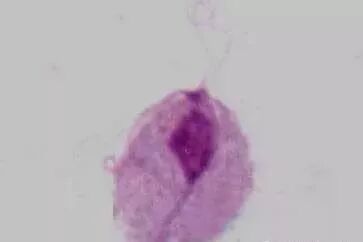

六、阴道毛滴虫

生理情况下,阴道pH为4~4.5,不适宜阴道毛滴虫生存(其最适pH为5.5~6.0),故不引起女性生殖道滴虫性阴道炎。

病理情况下,滴虫可寄生于阴道后穹隆,常引起滴虫性阴道炎,可合并邻近器官的感染,如尿道和尿道旁腺感染滴虫能利用上皮细胞内糖原作为能源进行直接分裂,主要传播途径是通过衣物和性交在男性,滴虫可寄生于包皮下、前后尿道、前列腺(最多见,占90%)、精囊内,可长时间持续存在,具感染性,经直接或间接方法传播。

阴道毛滴虫感染的发病率,在男性可达2%~15%,女性则达10%~2 5%男性常为携带者滴虫也引起泌尿道症状和不孕症